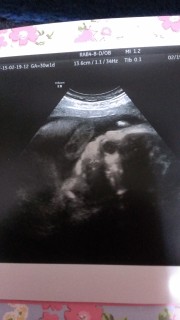

体重は今回教えてもらえませんでしたが、頭だけ二週~三週分大きいようです(笑)私も夫も頭は大きいので遺伝だねと言ってます(* ̄? ̄*) 今朝、検診だからお顔見せてねって言ってたら、バッチリ見せてくれて、声に反応してこっちを向いてくれる可愛い我が子(///ω///)♪